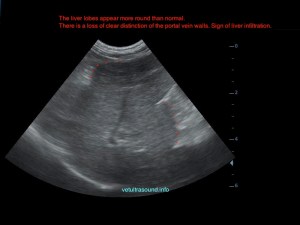

Ήπια ηπατομεγαλία με αύξηση της ηχογένειας του οργάνου, χωρίς παρουσία εστιακών αλλοιώσεων(pic.4). Πάχυνση του τοιχώματος της χοληδόχου κύστης με εικόνα βλεννοκήλης ( kiwi sign) και έντονη υπερηχογένεια στη περιοχή περί αυτού(pic.1&2). Ήπια διάταση της νεφρικής πυέλου, πιθανόν λόγω της πολυουρίας και πολυδιψίας(pic.3). Επασβέστωση στον οπίσθιο πόλο του δεξιού επινεφριδίου και αύξηση των διαστάσεών του(pic.6). Απουσία ασκιτικής συλλογής και παθολογικά διογκωμένων λεμφαδένων.